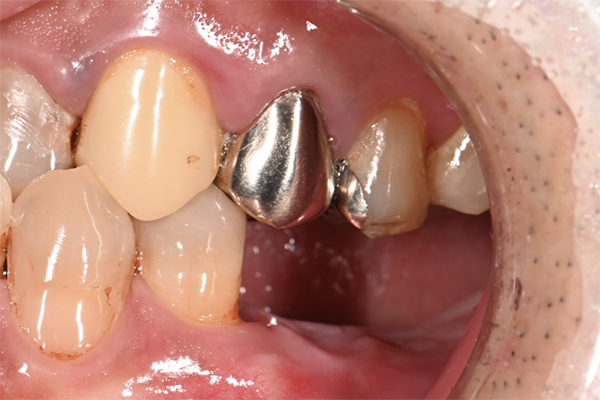

| 主訴 | 右上の奥歯を入れたい |

|---|---|

| 治療内容 | 右上第一大臼歯に対するインプラント治療 |

| 治療期間 | 4ヶ月 |

| 治療費 | 39万5千円 |

| 治療 リスク | インプラントの土台を入れた後最終的な歯が装着されるまで仮歯をしていただきます |